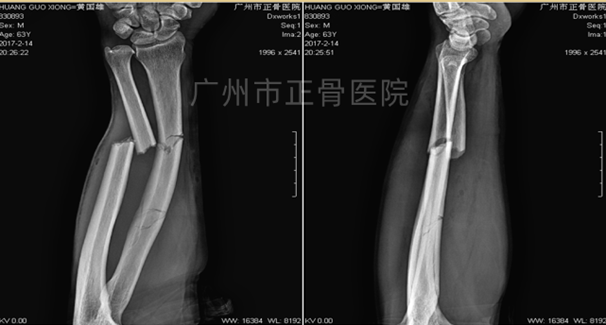

治疗:运用黄氏正骨手法复位骨折并以小夹板外固定,复查X线片提示骨折端位置良好。3天后复查X线见尺骨移位,调整后加石膏托固定,复查X线提示骨折端位线较前改善。1周后复查X线提示骨折稳定。维持石膏、夹板固定,继续复查换药,指导患者适当功能锻炼。6周后,可见轻微骨痂生长。2个月后骨折线部分模糊,2个半月后复查X线提示骨痂生长增多,骨折端稳定,拆除外固定,指导患者循序渐进进行功能康复锻炼。3个月后,患者功能恢复正常。1年后复查X线片,提示骨性愈合。

▲3天后复查见尺骨移位

▲手法调整后加石膏托固定